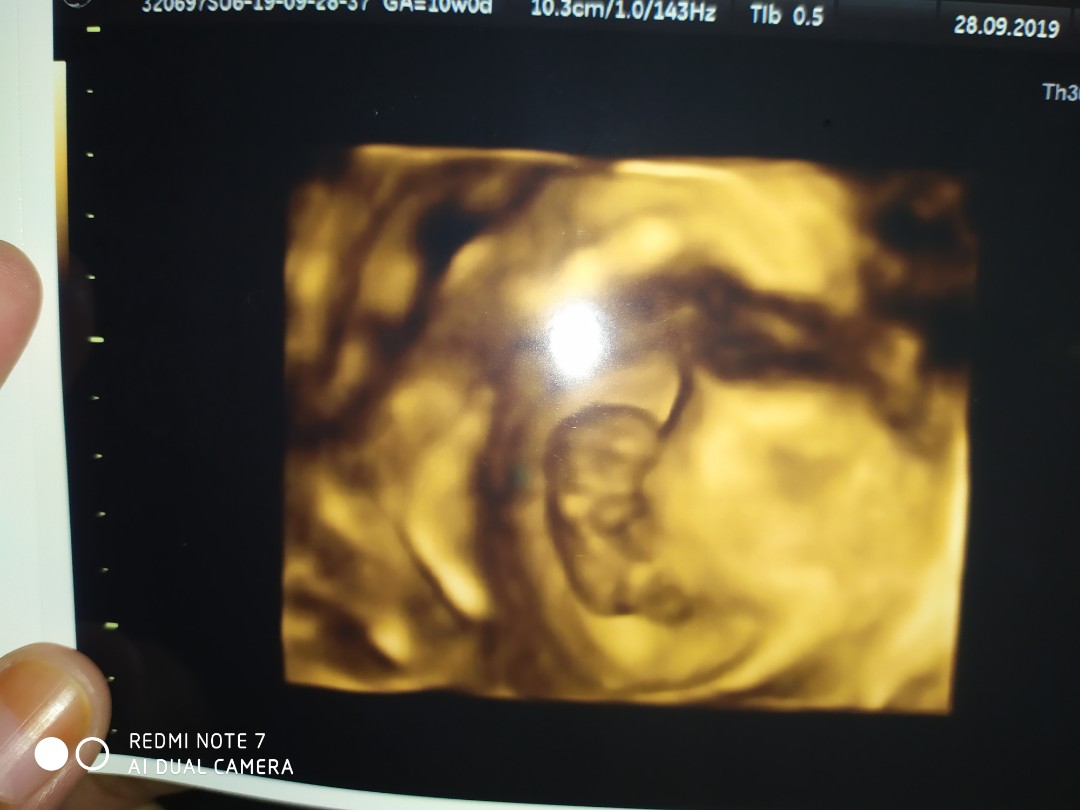

Ini usia 10w bun...